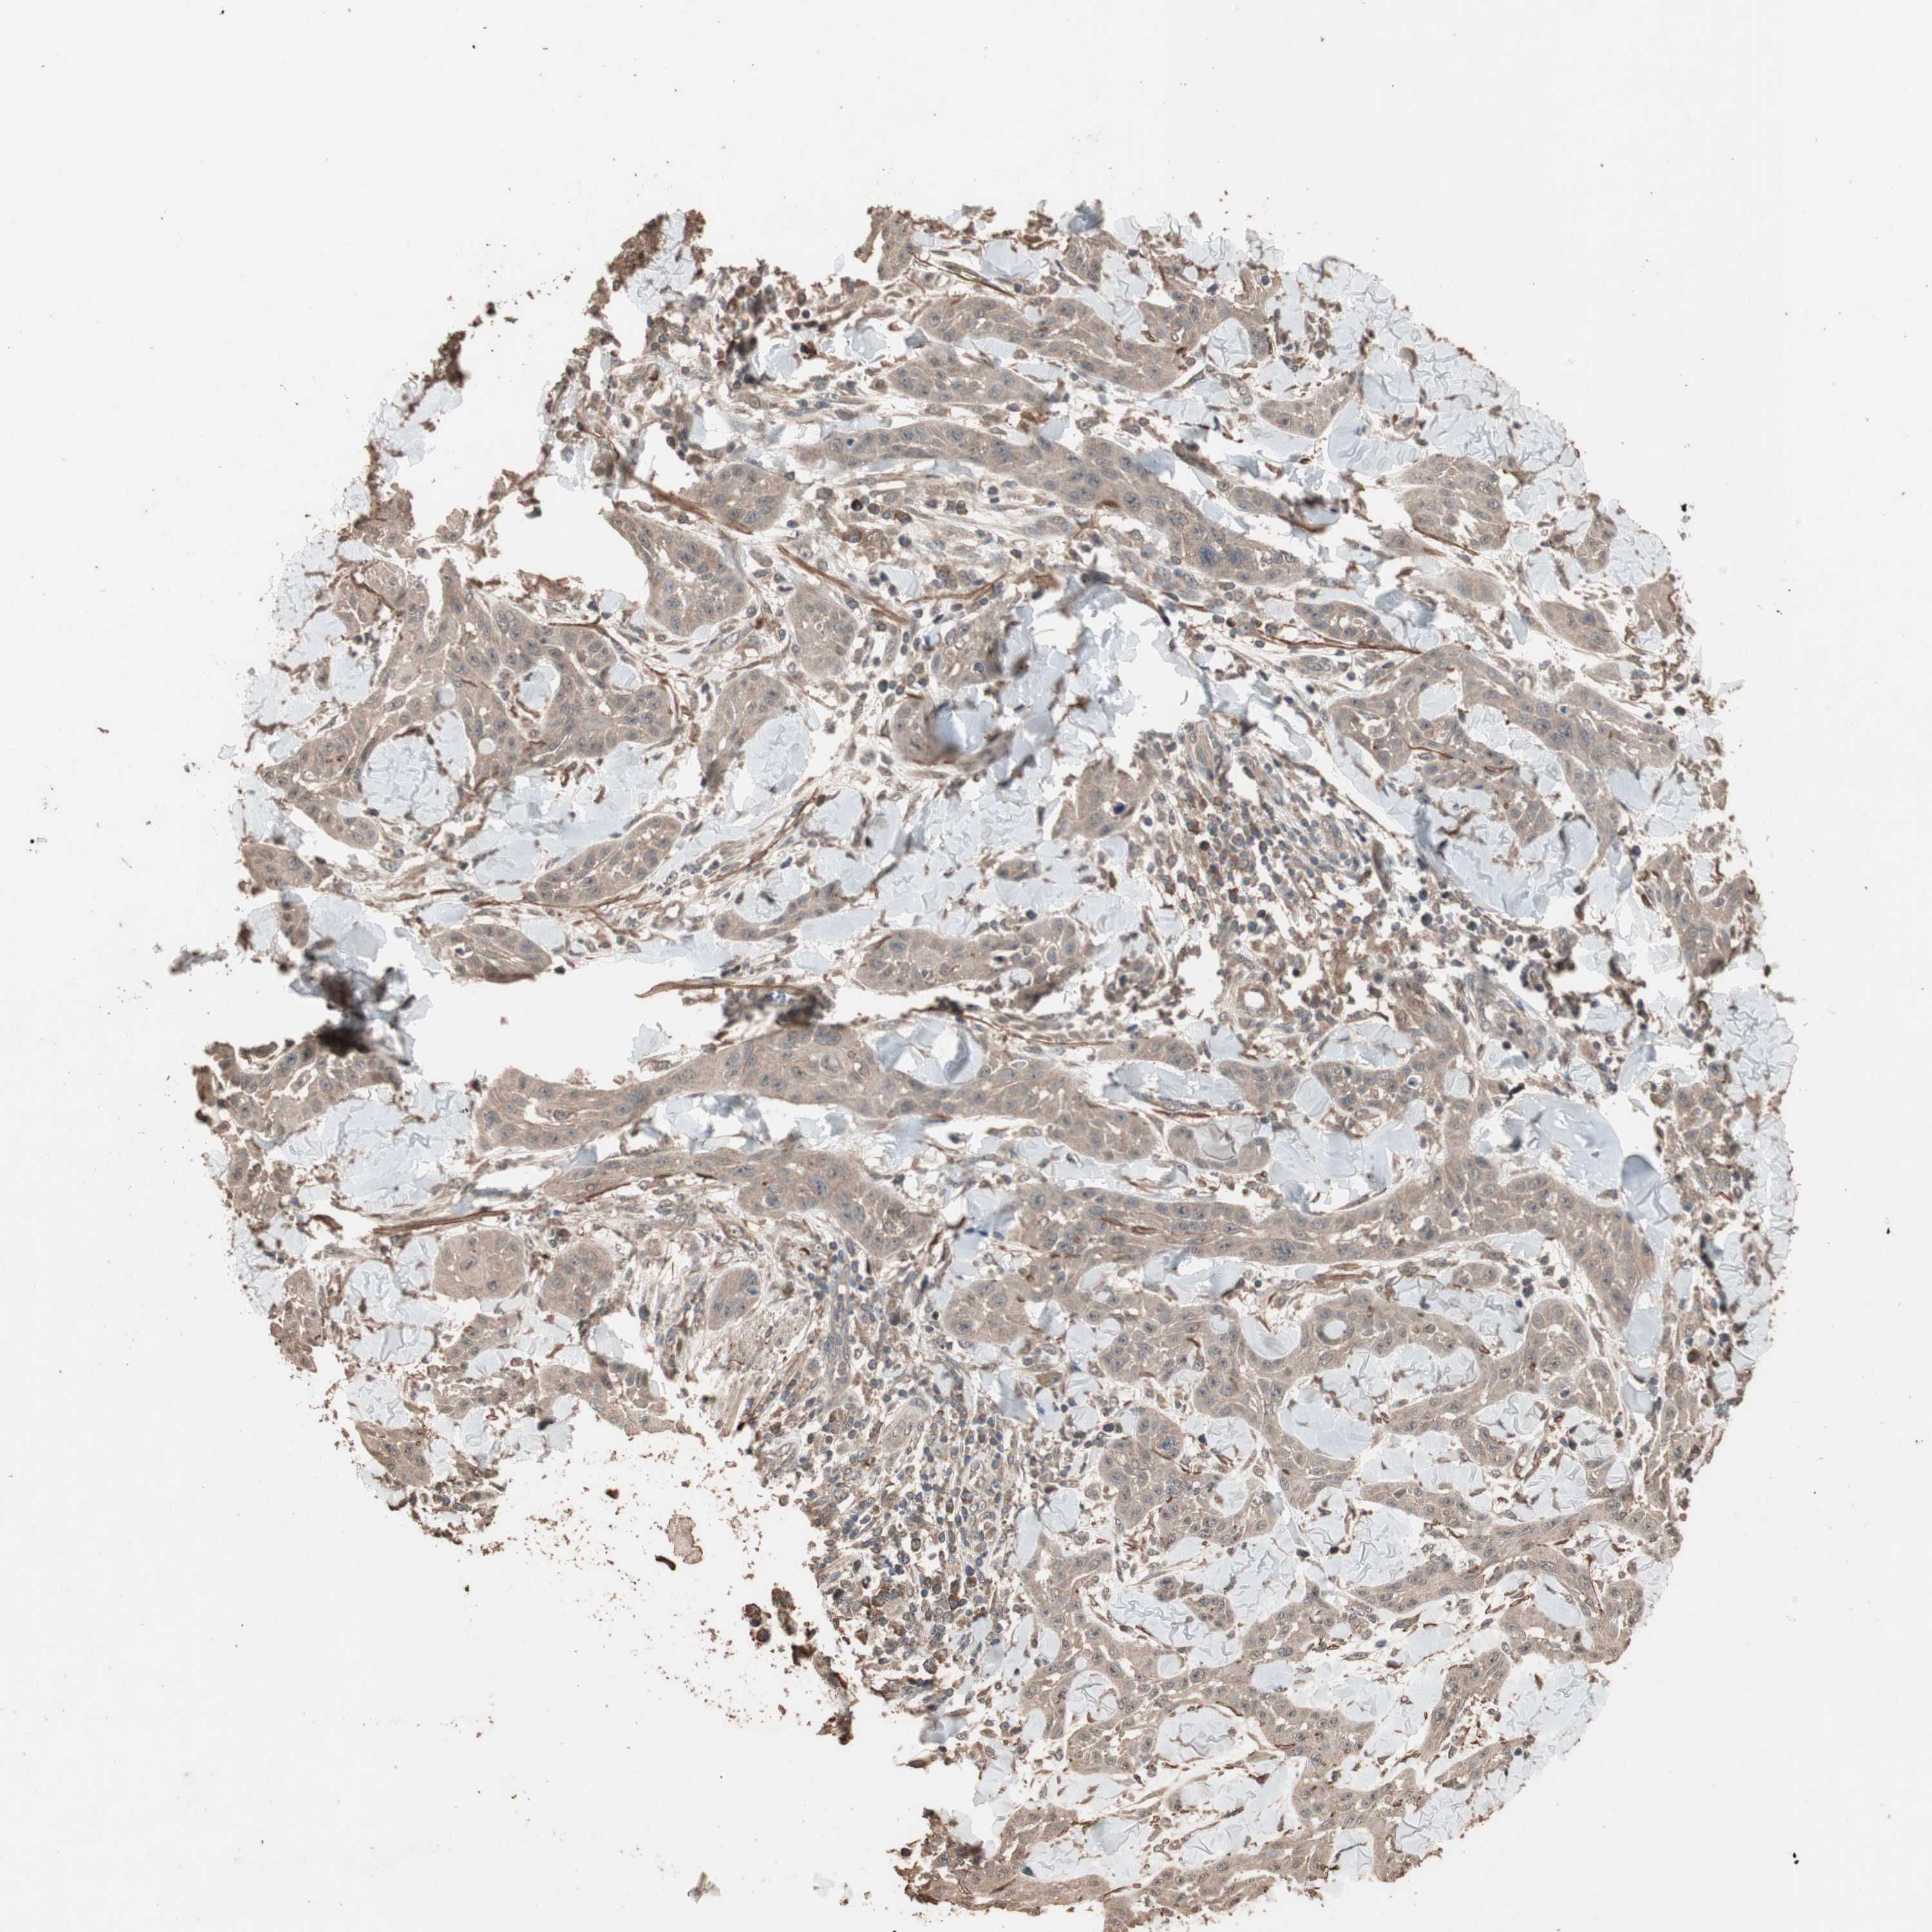

SKIN CANCER - Protein expressioni

A mouse-over function shows sample information and annotation data. Click on an image to view it in a full screen mode. Samples can be filtered based on level of antibody staining by selecting one or several of the following categories: high, medium, low and not detected. The assay and annotation is described here.

Each image is clickable and will lead to virtual microscopy that enables deeper exploration of all samples and also displays staining intensity scores, fraction scores and subcellular localization as well as patient and tissue information for each sample.

Antibody HPA006287

Staining

Not detected

Intensity

Negative

Quantity

None

Location

Basal cell carcinoma